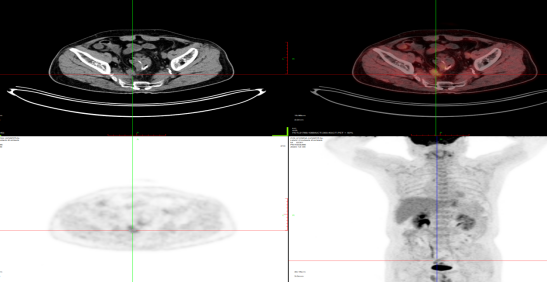

淋巴瘤治疗后2021-2-25 2021-7-24